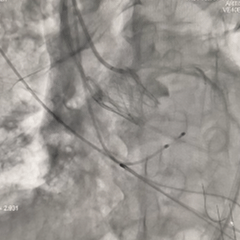

冠脉风险充分评估

调整至左头位再次造影,可见左、右冠显影可

使用左冠导管造影,可见左冠显影可

再次调整体位重新造影,可见右冠灌注正常。决定准备瓣膜脱钩释放

脱钩后造影

无窦侧深度约瓣上2mm,小弯侧深度基本零位,瓣膜植入位置尚可,瓣架形态呈现微倒梯形,可见少量瓣周漏,右冠显影正常

左冠切线位评估

左冠导管造影,可见左冠显影可,考虑导管挤压瓣叶可能,决定将导管拉出冠脉口再次造影评估

左冠再次造影评估

导管拉出左冠口后造影,可见冠脉灌注正常,瓣叶未超过冠脉开口